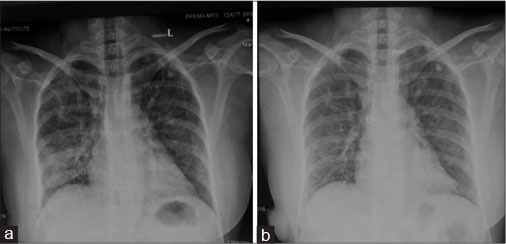

| Figure 1 Pretreatment X-ray showing interstitial infiltrates involving mid and lower zones (a) with significant resolution after treatment (b)